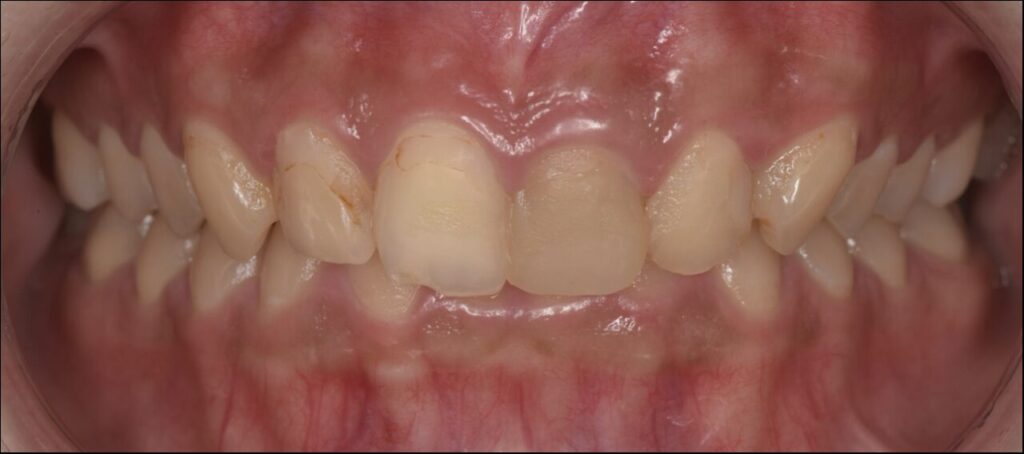

セラミック / 審美歯科

前歯のセラミッククラウンで治療した症例

Before

| 治療内容 | セラミッククラウン |

| 治療期間・治療回数 | 根管治療2回、セラミッククラウン2回 |

| 治療費用 | 170500円(税込) |

| 備考 | 治療方法や費用、治療期間などは、ケースによって異なります。患者さまに合わせた治療計画をカウンセリング時にご提案いたしますので、治療例は参考程度にご覧ください。 |